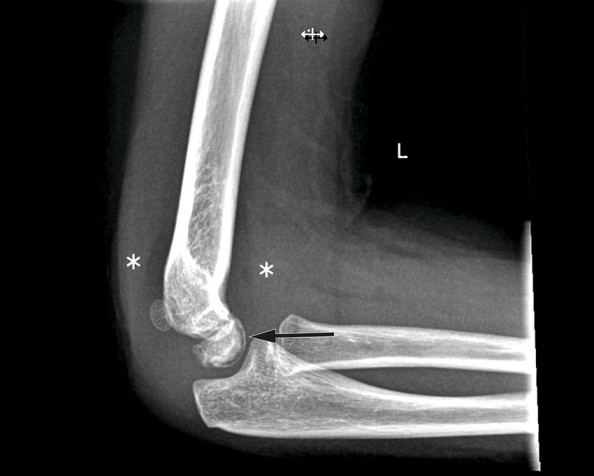

På røntgenbildet samsvarer oppklaringslinjen (markert med sort pil) med flere små gassbobler på samme sted på CT-bildet (hvit pil) - såkalt vakuumfenomen. Løftet fremre og bakre fettpute (markert med stjerner) er tegn på hydrops. Det er også litt ujevn benkontur ventralt i capitulum. Funn er typisk for Panners sykdom.

Røntgenbildet av venstre albue viser løftede fettputer som tegn på hydrops (markert med stjerner), men ingen synlig fraktur eller luksasjon. Det ses en tynn stripe med redusert bentetthet subkondralt i ventrale del av capitulum (sort pil), og på CT-bildet samsvarer linjen med flere små gassbobler på samme sted – såkalt vakuumfenomen. Det er også ujevn benkontur ventralt i capitulum. Funnene er typisk for Panners sykdom.

CT-bilde. Vakuumfenomen er markert med hvit pil.

Typiske kliniske funn ved Panners sykdom er smerte, hevelse, stivhet og innskrenket bevegelighet i albueleddet. Radiologisk kan man se morfologiske avvik, deform kontur, kollaps eller økt tetthet i capitulum (1). Subkondralt vakuumfenomen er et sjeldent funn, men er svært spesifikt for tilstanden. Vakuumfenomenet, som representerer subkondral gassdannelse, er et tegn på beniskemi og kan indikere aseptisk nekrose (1).